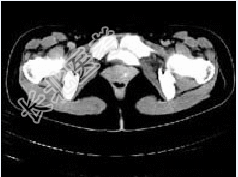

- 多项选择题女,28岁, 阴道有异常液体流下,CT和MRI扫描如图, 以下诊断正确的是( )

B、CT增强示造影剂由膀胱进入阴道

C、膀胱后下缘可见鸟嘴状突起

D、考虑为膀胱阴道瘘

E、考虑为左侧输尿管异位开口